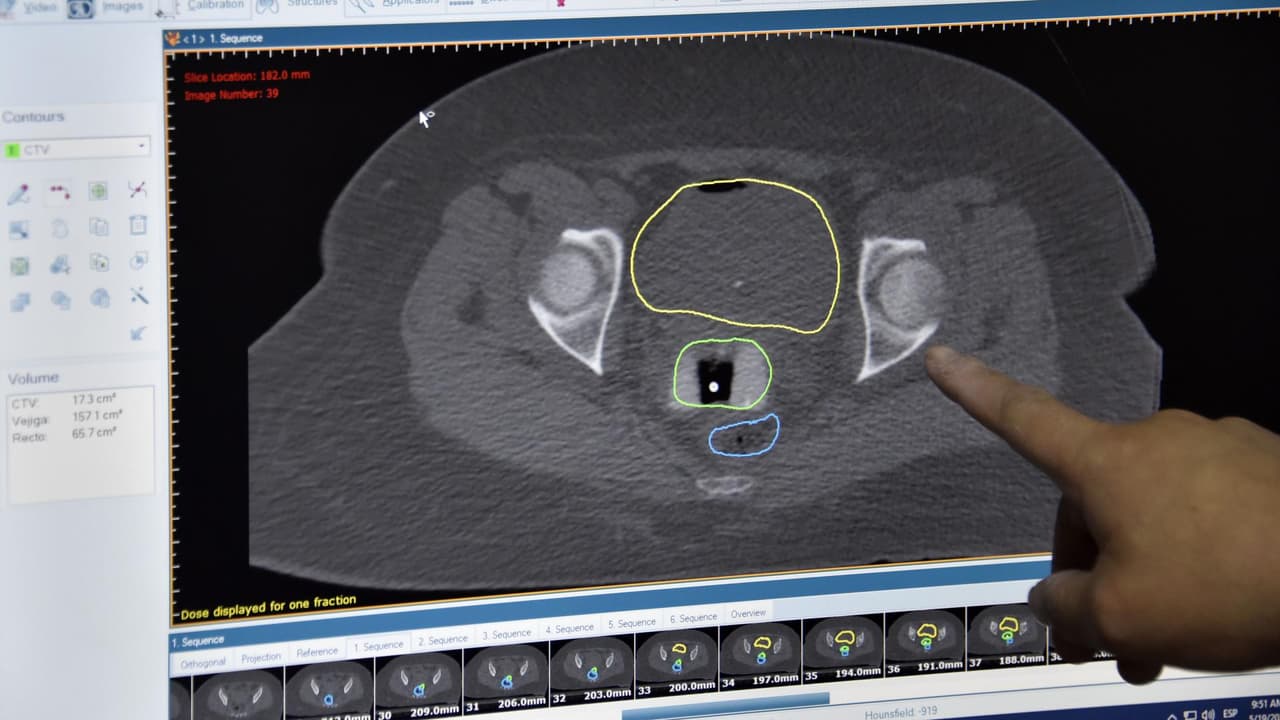

Anualmente en EEUU, cerca de 12,000 mujeres son diagnosticadas con cáncer de cuello uterino, por ello en el mes de concientización sobre la salud cervical el ginecólogo oncólogo del Hospital Stroger, Wilberto Nieves, explica que este tipo de tumores es el que más se puede prevenir por medio de la citología y con la vacuna del virus del papiloma humano (HPV). Por otra parte, el especialista señala que el tratamiento varía según la etapa del diagnóstico. Te explicamos.